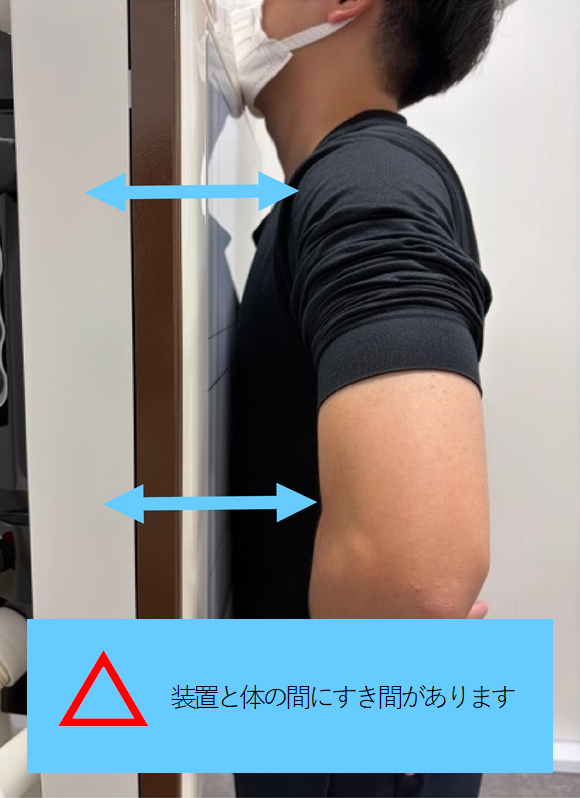

ポイント① アゴを上に向けて、体を装置に近づける

Ⓐアゴは軽く上向き

台に載せなくてもOK!

(背伸びはNG)

Ⓑ手は腰の横

手の平は外向き